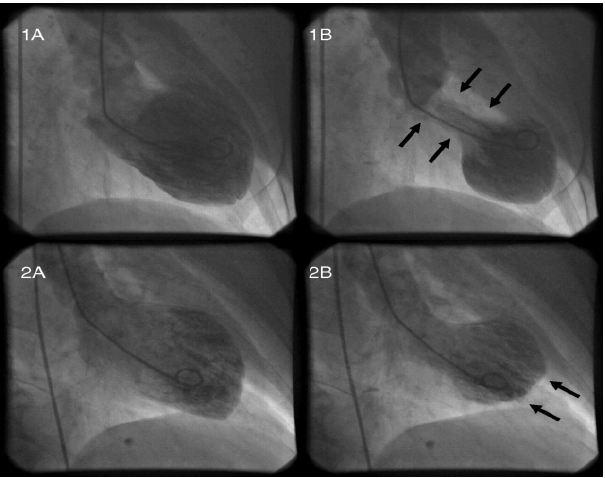

Mulher 55 anos, hipertensa, após a morte de seu filho evolui com dor torácica em aperto com irradiação para braço esquerdo. Ao procurar atendimento médico, realizou exames que evidenciaram níveis de troponina elevados e seu eletrocardiograma foi normal. Levada ao cateterismo, observa-se que suas coronárias eram normais, porém havia alteração de seu ventrículo. Este estava com hipocinesia, médio e apical associada a hipercinesia compensatória basal.

Qual provável diagnóstico desta paciente: